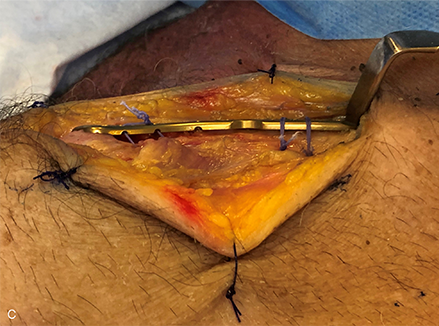

Distal clavicular fractures are characterized by splitting of fragile bone in a horizontal plane as well as vertically, with fragments which are often closely associated through the soft tissues around the fracture zone. Fixation of these fractures requires complex and variable orientation of fixation in the weaker distal bone and optimal balanced fixation in the stronger diaphyseal bone while respecting the trapezius, deltoid, and pectoral muscle attachments and permitting repair and reconstruction of coracoclavicular ligaments where required. Low-profile fixators are tolerated better, screw head prominence should be avoided, and fixation in the shaft should not compromise fixation in the distal clavicle, and vice versa. A prototype fixator used in a user-evaluation laboratory is shown in Figure 1.

Figure 1a–c Distal clavicular fixation during prototype evaluation of the novel VA Clavicle System. Lateral is to the left in all figures. Conformation of the plate to the superior topography of the distal clavicle is designed to facilitate positioning of the distal margin of the plate parallel to the acromioclavicular joint (a) and respects the almost universal 12o downward tilt of the distal clavicle in the lateral fifth of the bone (b), while also allowing the plate to follow the beginning of the twist region at the junction of the second and third fifths of the bone (c).